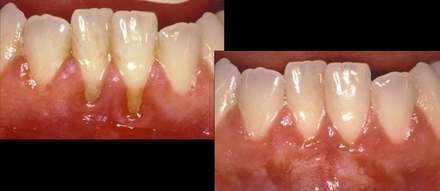

A gingival tissue graft will restore the proper gum tissue structure around the tooth.